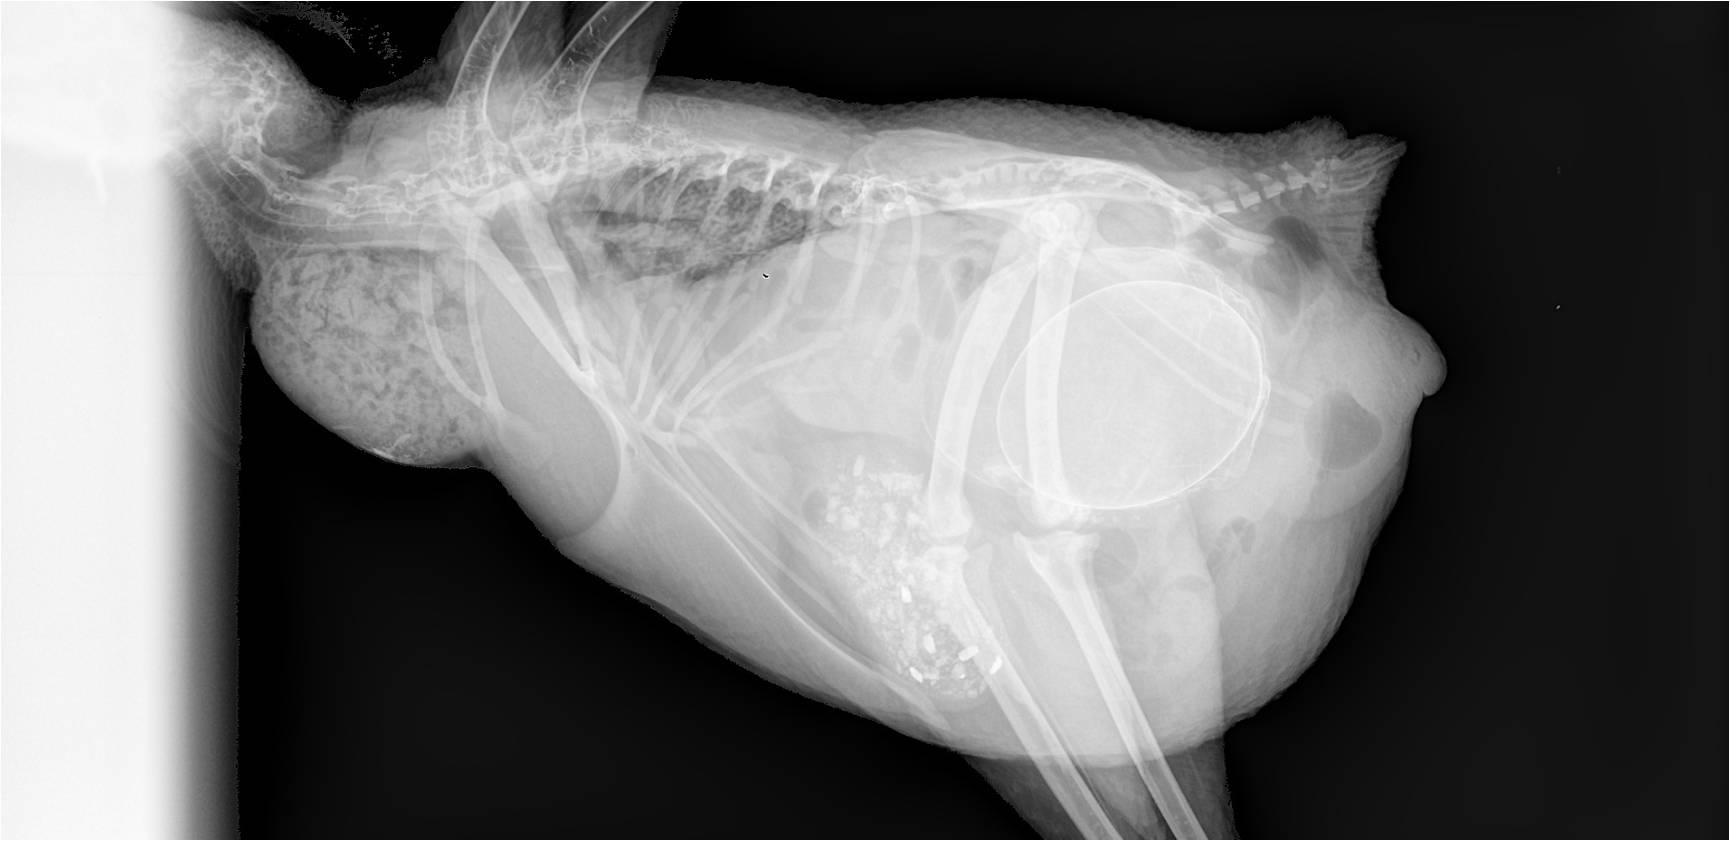

L'arrêt de la ponte peut être naturelle en hiver et certaines races sont aussi moins prolifiques que d'autres. Néanmoins, l'arrêt de la ponte peut également être un signe de maladie grave, telle qu'une rétention d'oeuf ou une impaction de l'oeuf dans le corps de la poule. Cela produit alors une infection de l'appareil reproducteur (une salpingite) ou des pontes ectopiques (ponte d'un oeuf à l'intérieur du corps). Le diagnostic fait souvent appel à des moyens d'imagerie (radiographie, échographie) et le traitement est généralement chirurgical avec une chirurgie coelomique de salpingectomie.